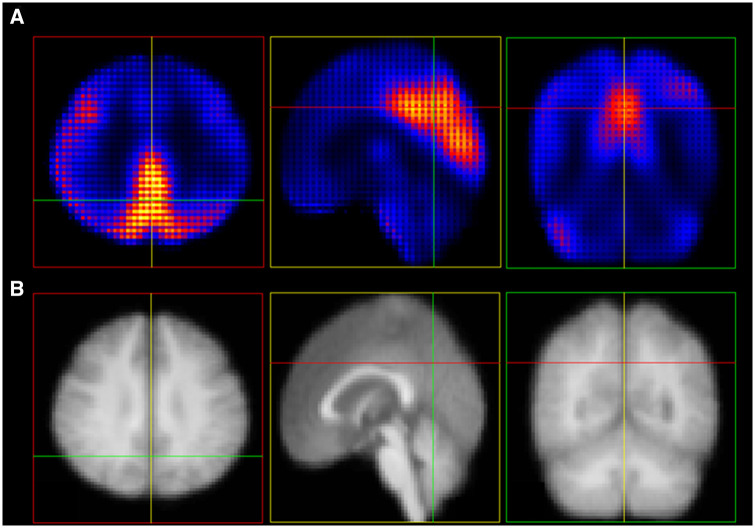

Background: With disease-modifying treatments for Alzheimer's disease (AD), prognostic tools for the pre-dementia stage are needed. This study aimed to evaluate the prognostic value of an 18F-fluorodeoxyglucose-positron emission tomography (18F-FDG-PET)-based deep-learning (DL) model in the pre-dementia stage of mild cognitive impairment (MCI) and normal cognition (NC).

Materials and methods: A 18F-FDG-PET-based DL model was developed to classify diagnosis of AD-dementia vs NC using AD Neuroimaging Initiative (ADNI) and Japanese-ADNI (J-ADNI) datasets (n = 756), which provided the degree of similarity to AD-dementia. The prognostic value of the DL output for cognitive decline was assessed in the ADNI MCI (n = 663), J-ADNI MCI (n = 129), and Harvard Aging Brain Study (HABS) NC (n = 274) participants using Cox regression and calculating the integrated area under the time-dependent ROC curves (iAUC), along with clinical information and 18F-FDG-PET standardized uptake value ratio (SUVR). Subgroup analysis in the amyloid-positive ADNI MCI participants was performed using Cox regression and calculating the area under the time-dependent ROC (tdAUC) curves at 4-year follow-up to assess prognostic value of DL output over clinical information, 18F-FDG-PET SUVR, and amyloid PET Centiloids.